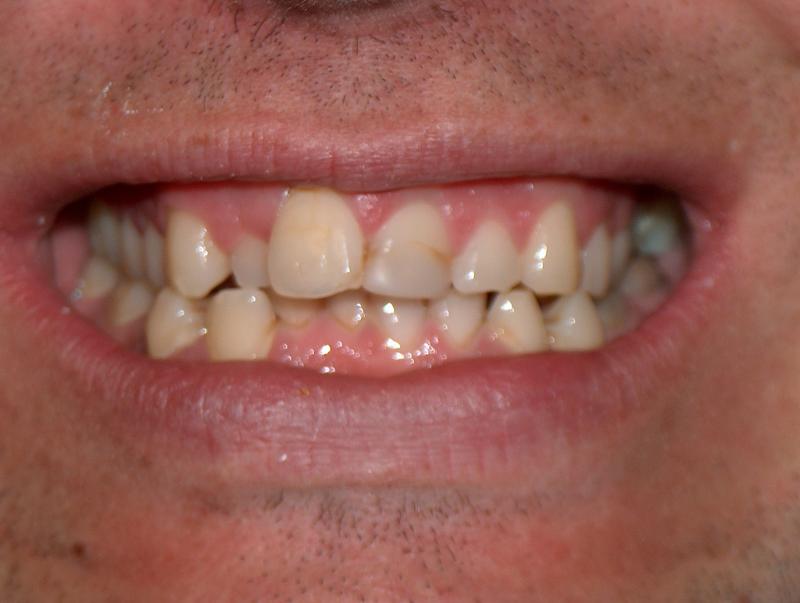

Steve N.

Invisalign Case

INVISALIGN, 16 months, 2 series of aligner to correct the anterior cross bite, to intrude the over erupted and extremely crowded lower incisors. COSMETIC DENTISTRY, leveling of incisal edges, gingival tissue contouring, and cosmetic bonding.

Cosmetic Dentistry, Mid-line Asymetry, Severe Crowding